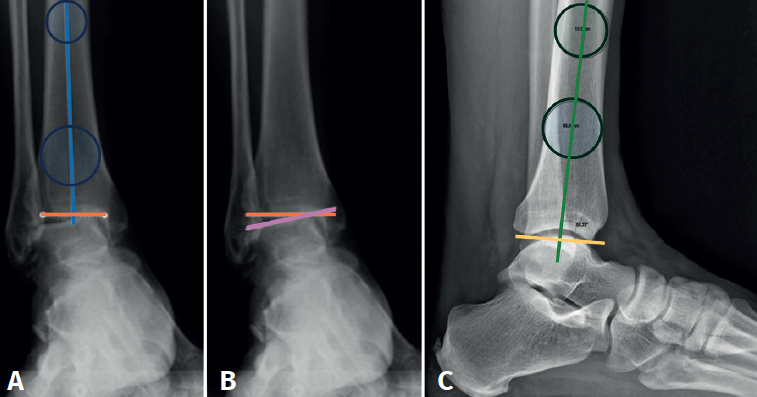

As with any ankle joint procedure, it is mandatory to analyze proximal alignment, infra-malleolar alignment and intra-articular misalignment.

The plain radiographic study should include posteroanterior and lateral views of the ankle and foot under weight bearing conditions, and a mortise projection. We must also have telemetry of the limb to assess proximal alignment and a Saltzman or long axial view to assess infra-malleolar alignment(14).

The supra-malleolar alignment of the ankle should be evaluated in the coronal and sagittal planes, measuring the anterior distal tibial angle and the lateral distal tibial angle, respectively.

In the anterior ankle projection we evaluate the talar tilt or angle of inclination of the talus, which is increased in incongruent intra-articular injuries (Figure 1).

Hindfoot alignment must be accurately assessed, considering the correction of axial deviations before or in conjunction with any tibiotalar fusion procedure.

We must observe whether, in the lateral projections, there is an anterior translation of the talus, which often occurs in these chronic degenerative phenomena associated with instabilities (Figure 2).

Computed tomography (CT) and single photon emission tomography (SPECT)-CT are the most useful complementary tests to plain radiography, since they allow characterization of the osteoarticular lesions both in the ankle and in the rest of the neighbouring joints, as well as the evaluation of alterations in the different bone structures (osteophytes, bone cysts, loss of bone stock , etc.). Some studies argue that SPECT-CT has significantly higher inter- and intra-observer reliability compared to CT(15).